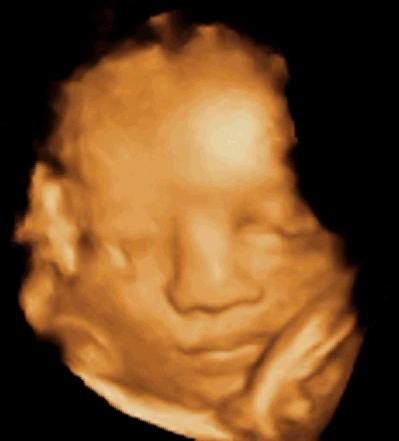

А вот и 3D-скан 33-недельного ребенка…

На этой неделе рост вашего ребенка от головы до пяток составляет 43,7 см — длина этого классического торта M&S.

Теперь ваш ребенок весит около 4 фунтов 6 унций (2 кг)!